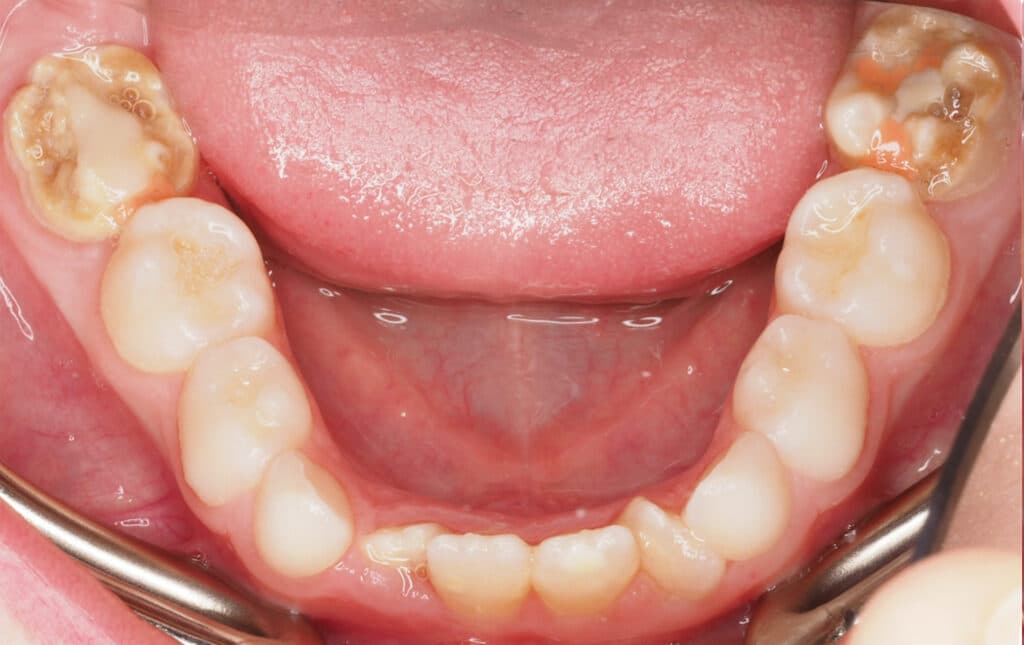

Does your child have “chalky teeth”? Perhaps one or more of your child’s adult teeth have come through with white, yellow or brown patches – or with a mottled appearance. The teeth may seem weaker than usual, with enamel that looks malformed, or fragile. If this sounds familiar, you’re not alone. In this blog, we’ll […]